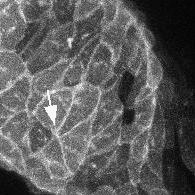

„Gewöhnlich beobachten wir, dass das Zytoskelett in den Herzzellen nicht überall gleich aussieht, sondern eine Polarität aufweist“, sagt Merks: „An der Oberfläche der Zellen ist es anders gestaltet als an deren Basis.“ Ist der PCP-Signalweg beeinträchtigt, geht diese Polarität verloren. Als Folge davon findet das schlauchförmige Herz nicht recht zu seiner neuen Form. „Insbesondere der Ausflusstrakt des Herzens kann sich dann nicht richtig bilden“, sagt die Forscherin. Ein Großteil der angeborenen Herzerkrankungen geht auf Störungen in diesem Teil des Organs zurück.